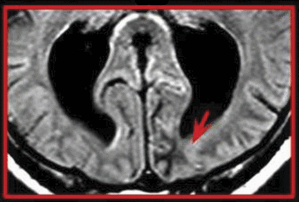

这个问题特点2临床推理病例:第一个提出了人与复发性失语症,头痛、混乱和突出维护一个广义微分的重要性,包括治疗感染尤其是患者免疫抑制。第二个讨论如何方法治疗急性疾病患者肌无力的危机可能的冠状病毒2019 (COVID-19)。教学实验描述nonketotic高血糖的hyperosmolar状态,一个重要的中风模拟(见特色形象)。在神经影像学教学视频,三个癫痫患者痉挛眼科诊断是Aicardi综合症基于特征的发现包括视网膜脉络膜缺损。

教学实验:Nonketotic高血糖的hyperosmolar国家模仿急性缺血性中风

这种情况下的55岁的人强调急性缺血性中风模仿nonketotic高血糖的hyperosmolar状态。